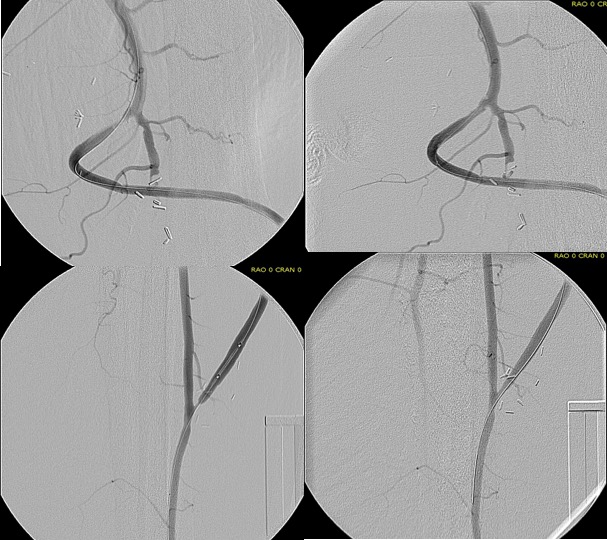

My eye focused on the left iliac graft which perfused the internal iliac artery on that side. The graft was generous, and likely a dilated 8mm graft, and could be exposed via a left lower quadrant retroperitoneal exposure (the transplant exposure). This would allow me to to then tunnel to avoid the terribly scarred groins. On the right side, the obdurator canal could be traversed into the postioer compartment of the thigh -a graft could be sent to the below knee popliteal artery with a side graft to the tiny profunda femoral artery. On the left, the graft could be tunneled laterally near the insertion of the sartorius muscle and onto the superficial femoral artery. All of the incisions would be made in virgin skin, the only redo dissection being digging out the left iliac graft while avoiding injury to the ureter.

The bladder was dissected off the pubis to allow the graft to be tunneled to the right pelvis. A counter incision in the right lower quadrant abdomen and a mid thigh incision mobilizins the anterior compartment muscles to the posterior compartment allowed me to tunnel across the obturator foramen. The obdurator vessels need to be avoided or there will be bleeding. this mid thigh incision allowed exposure of the profunda femoral artery more proximally and allowe the graft to be tunneled anatomically to the below knee popliteal artery for anastomosis. A jump graft was taken off this graft on the thigh to the profunda femoral artery which was small and diseased -no more than 2mm in size. An axillary bypass to this profunda would be doomed to the compromised patency rate published for ax-fem bypasses giving them a bad name. The left superficial femoral artery was exposed and provided outflow to the left iliofemoral bypass which was tunneled far laterally under the inguinal ligament to avoid the scar tissue where the common femoral artery was.

There was immediately multiphasic signal in both feet on release of clamps. After closure of all the incisions and dressings, the right middle toe was amputated.